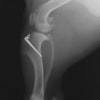

本症例は、走った後に左後肢を挙上していることを主訴に来院されました。触診時に左膝関節のクリック音を聴取、レントゲン検査にて左脛骨の前方変位が認められました。術中に、前十字靱帯の断裂及び内側半月板の損傷、内側の軟部組織の顕著な腫脹を確認。半月板切除、TPLOを実施しました。周囲組織への炎症の波及もあったため回復に時間を要しておりますが、徐々に跛行頻度は減少傾向にあり、現在も経過観察中です。術前に約29°あったTPAは術後に約10°まで矯正されました。

術前写真

術後写真

手術前後のTPA(脛骨高平部の角度)を測定しています。

約29°から約10°へ矯正されています。